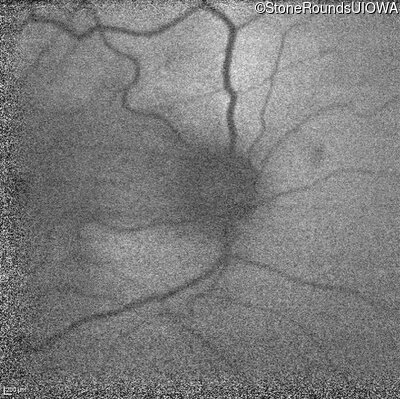

Age at visit:

60 years

OD

OS

20/200 -1 sc

OCT Stack

10/120 +1 sc